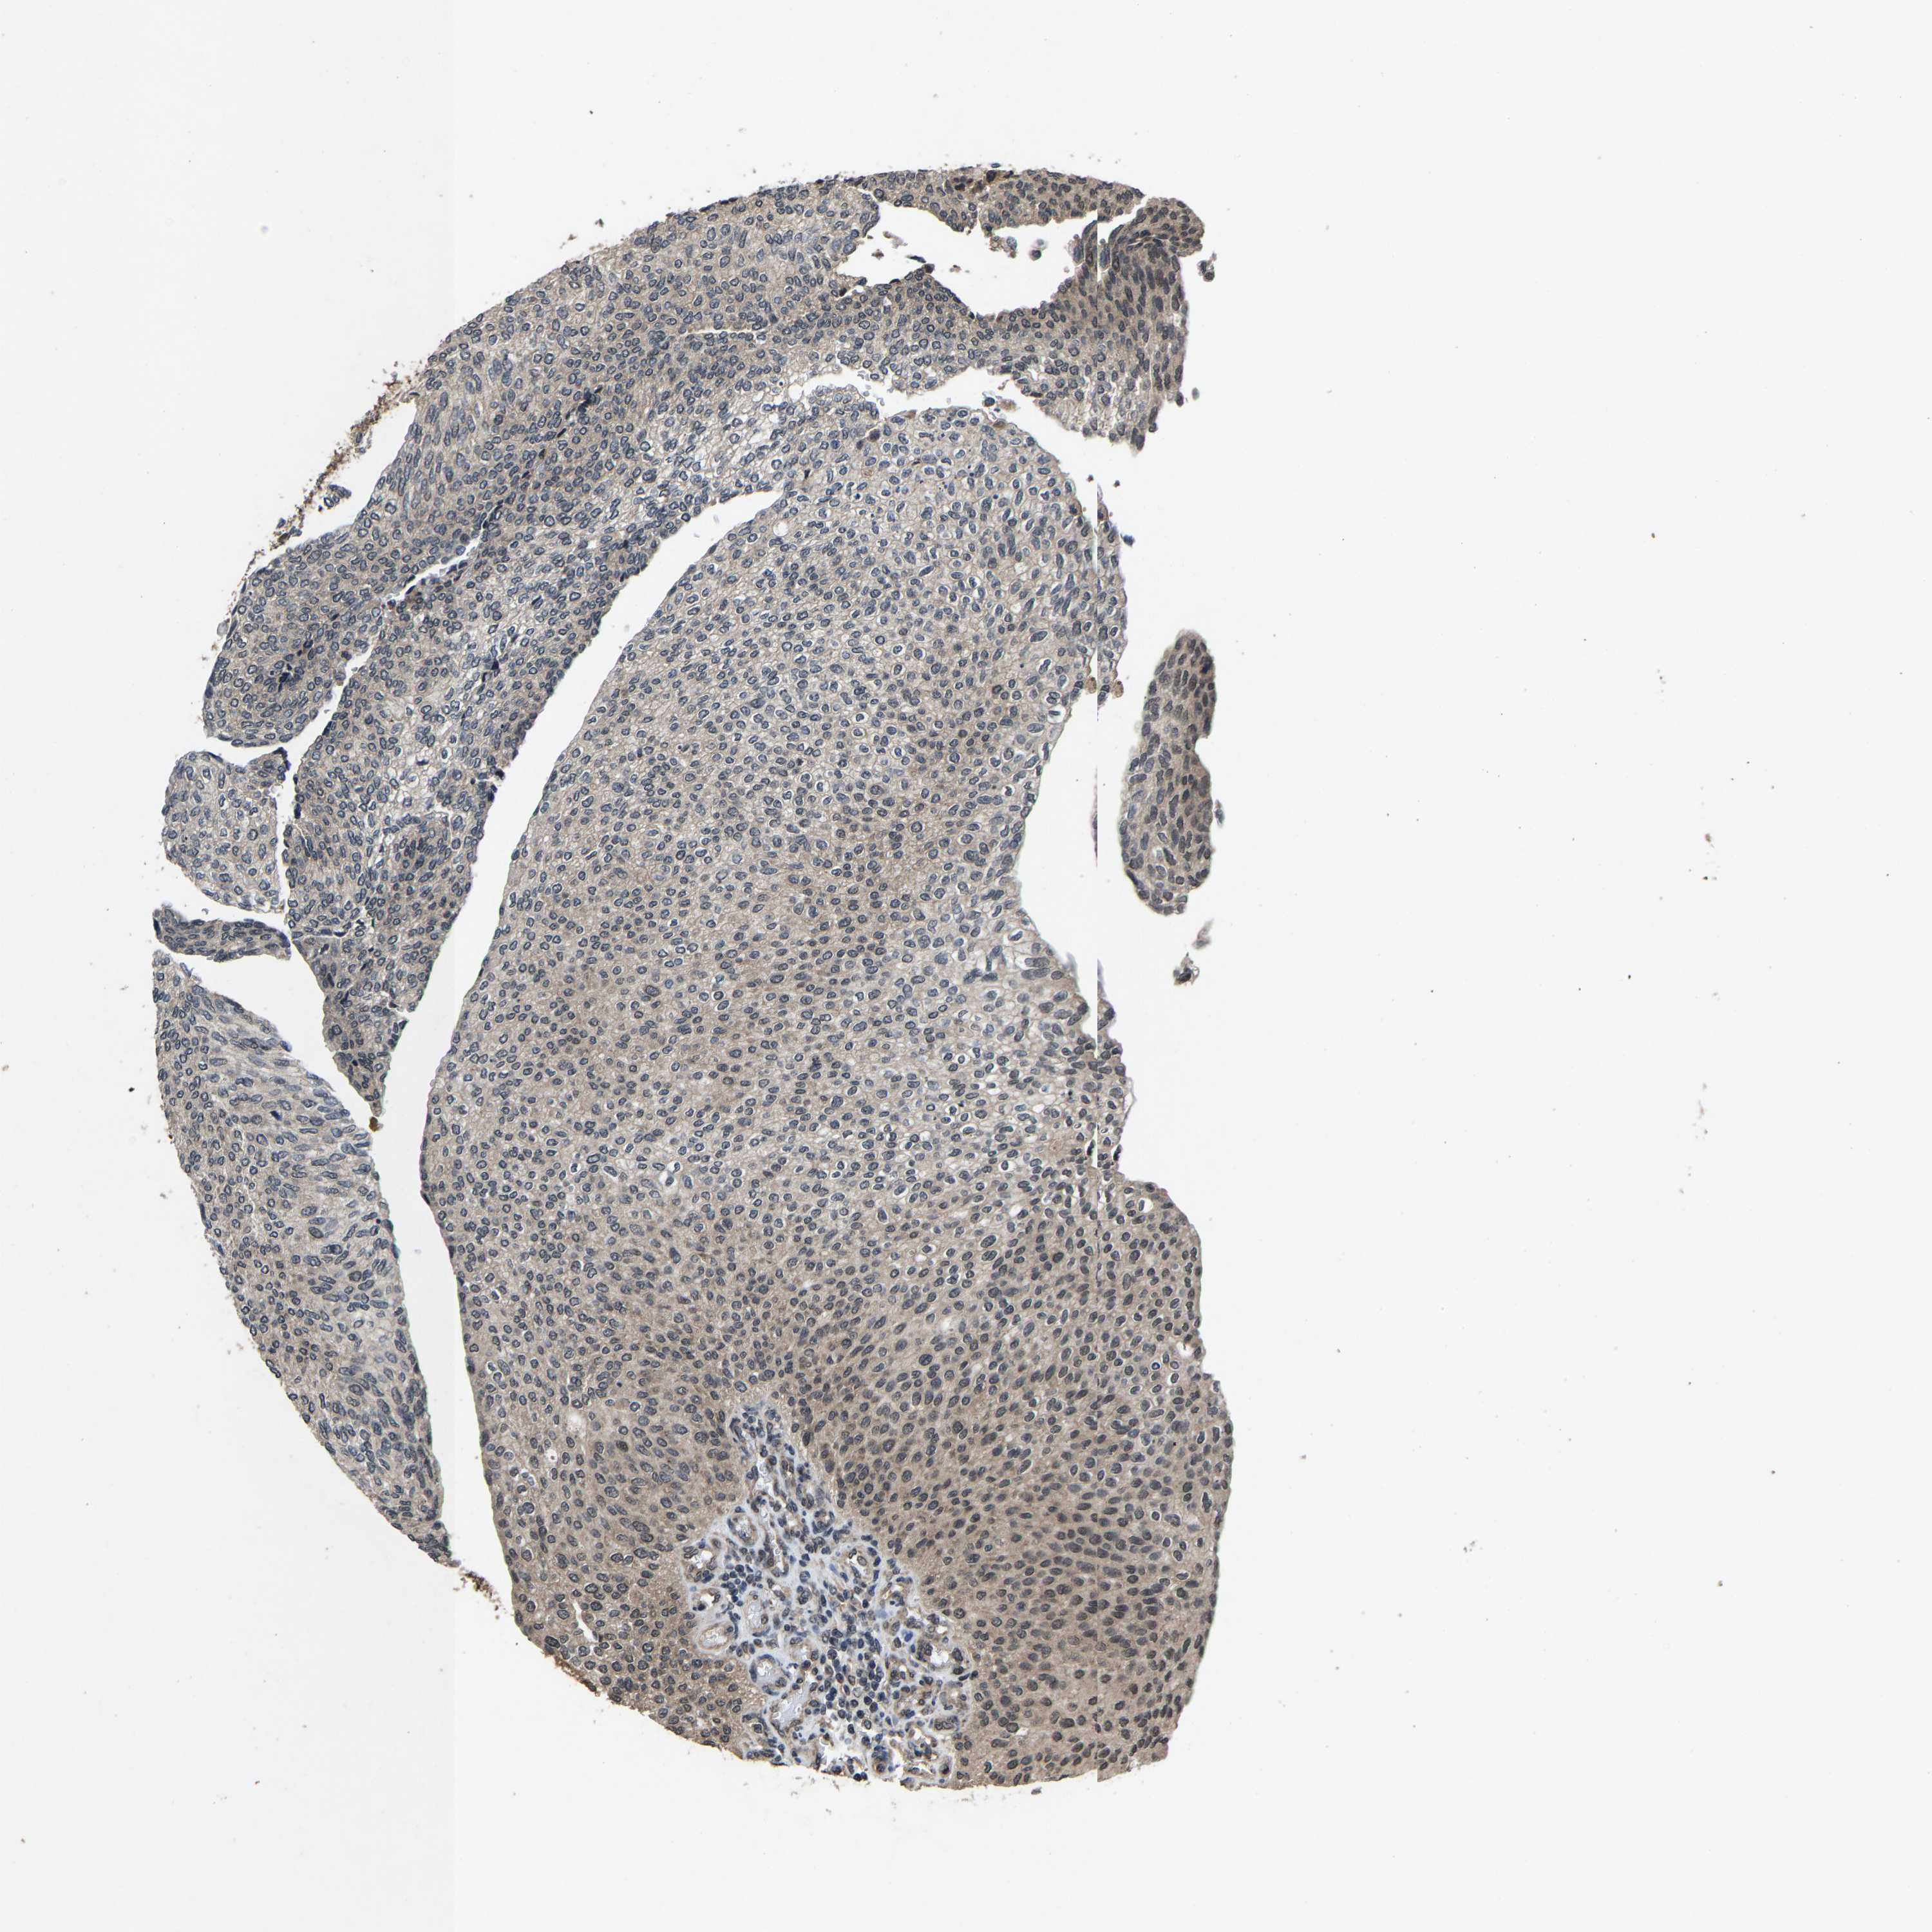

UROTHELIAL CANCER - Protein expressioni

A mouse-over function shows sample information and annotation data. Click on an image to view it in a full screen mode. Samples can be filtered based on level of antibody staining by selecting one or several of the following categories: high, medium, low and not detected. The assay and annotation is described here.

Note that samples used for immunohistochemistry by the Human Protein Atlas do not correspond to samples in the TCGA dataset.

Antibody stainingi

Antibody staining in the annotated cell types in the current human tissue is reported as not detected, low, medium, or high, based on conventional immunohistochemistry profiling in selected tissues. This score is based on the combination of the staining intensity and fraction of stained cells.

Each image is clickable and will lead to virtual microscopy that enables deeper exploration of all samples and also displays staining intensity scores, fraction scores and subcellular localization as well as patient and tissue information for each sample.

Antibody HPA002548

Antibody CAB022718

Staining

High

Medium

Low

Not detected

Intensity

Strong

Moderate

Weak

Negative

Quantity

>75%

75%-25%

<25%

None

Location

Nuclear

Cytoplasmic/membranous

Cytoplasmic/membranous,nuclear

Urothelial carcinoma, High grade

Urothelial carcinoma, Low grade

Adenocarcinoma, NOS